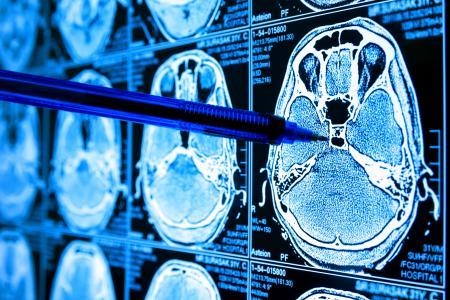

GLIOBLASTOME : Ensemencement et traitement à partir d’un site distant ?

Cette étude d’une équipe du Children’s National Hospital, Washington montre que les tumeurs cérébrales peuvent être ensemencées à partir d'un site distant. Ainsi, les cellules de glioblastome semblent provenir d'un pool de cellules souches, situé au départ dans la zone sous-ventriculaire (SVZ) à distance significative de la tumeur résultante. Ce constat, documenté dans la revue Nature Communications, ouvre 2 opportunités, traiter ce site distant pour empêcher l’ensemencement des cellules précurseurs de tumeur ou cibler la voie biologique qui favorise leur propagation.

Le glioblastome est un type agressif de cancer du cerveau, qui « en dépit de décennies de recherche, reste la tumeur cérébrale primaire la plus courante et la plus mortelle chez les adultes, avec une survie médiane de seulement 15 mois à compter du diagnostic », rappelle l’auteur principal, le Dr Yuan Zhu, du Children's National : « Contrairement à de nombreux cancers, qui commencent comme des tumeurs de bas grade plus faciles à traiter en cas de détection précoce, les glioblastomes sont presque toujours diagnostiqués à haut grade et difficiles à traiter quel que soit la technique, chirurgie, radiothérapie ou chimiothérapie. Cependant ces travaux, menés sur la souris modèle de tumeur cérébrale, laissent espérer de nouveaux traitements, qui vont cibler cette niche distante de cellules souches voire même une zone de surveillance « intermédiaire » pour empêcher le glioblastome de se développer.

La zone sous-ventriculaire (SVZ) est ici identifiée comme le site distant qui sert de réservoir de cellules souches avec les mutations cancérigènes qui sont retrouvées dans les tumeurs localisées dans d'autres régions souvent éloignées du cerveau. Ce constat est réalisé sur des souris génétiquement transformées pour présenter une mutation dans un gène connu sous le nom de p53 qui supprime généralement les tumeurs. Les mutations de p53 vont donc favoriser le développement du glioblastome et de nombreuses autres formes de cancer. Surveillés par scintigraphies cérébrales hebdomadaires, la majorité de ces animaux ont développé des tumeurs de haut grade dans plusieurs zones cérébrales éloignées. Les scientifiques sont parvenus à retracer les cellules qui ont stimulé les tumeurs jusqu'à la SVZ. Qu’elles soient simples ou multiples, les tumeurs présentent des mutations acquises spontanément dans un gène appelé Pten, un autre type de suppresseur de tumeur.